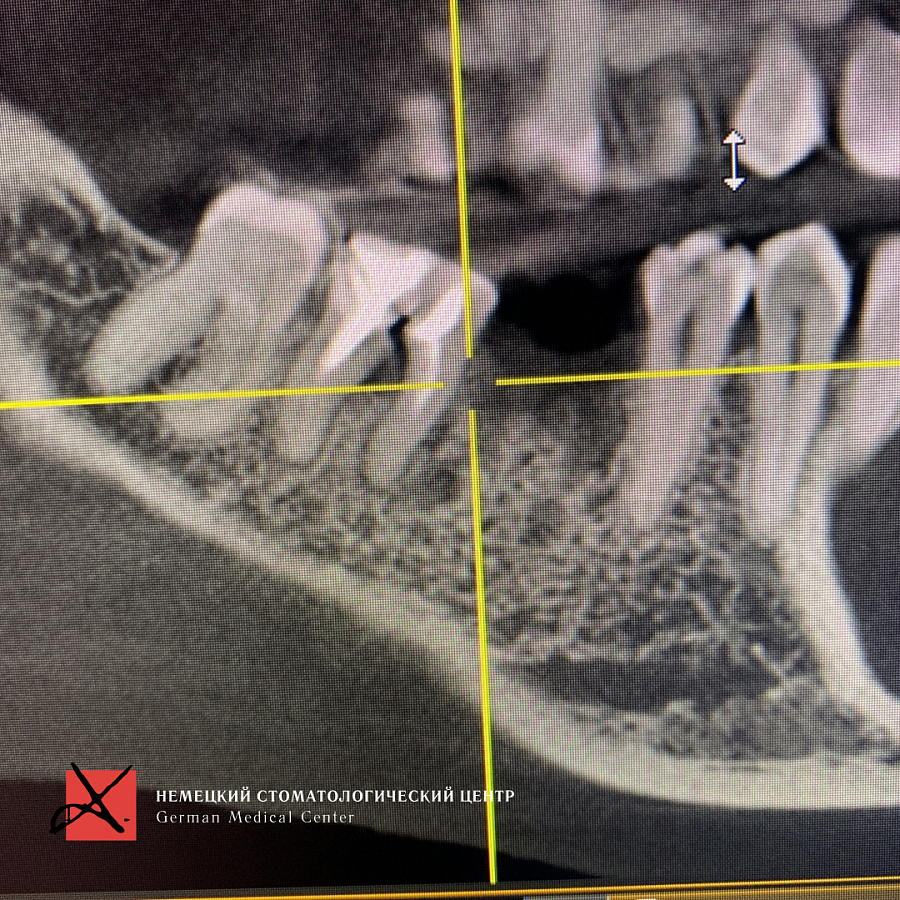

Пациентка обратилась с жалобой на перелом зуба, который ощутила при накусывании.

Провели имплантацию при помощи хирургического шаблона, который позволяет максимально точно спроектировать и спозиционировать положение имплантата для будущей функциональной нагрузки, грамотного распределения давления на имплантаты, а также здоровья зубного импланта. Операция прошла успешно.